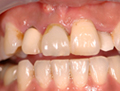

5:装置の装着 |

人工歯を装置して完了です。 |